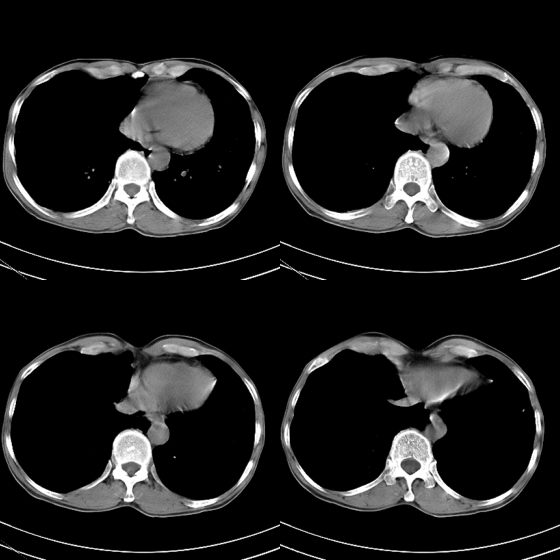

标题: CT21797:M65y,矽肺团块内空洞?

m65y,咳嗽、咯痰,煤工工作史10+年。低热,无明显脓臭痰。临床怀疑tb。

矽肺伴结核 右侧气胸,左肺上叶肺大泡

煤工尘肺,多发肺大泡,右侧气胸.

结合临床考虑尘肺并空洞形成,双肺多发肺大泡,右侧气胸。

矽肺伴结核(左肺上叶病灶内空洞形成),右侧气胸,两肺多发性肺大泡。

考虑矽肺伴结核,右侧气胸,左肺上叶肺大泡。

告病重没有?这种气胸不易复张,咳嗽剧烈左肺大泡再破就难活了。煤尘肺常继发结核,影像学不易鉴别。有结核的可疑临床症状,ppd5u皮试阳性,特别是强阳性,就有诊断性抗痨治疗指针。不过排他性诊断是最重要的。左上空洞内液平就不是结核应有的。同意9楼楼主看法,同时注意合并感染的问题,抗炎覆盖广一点。